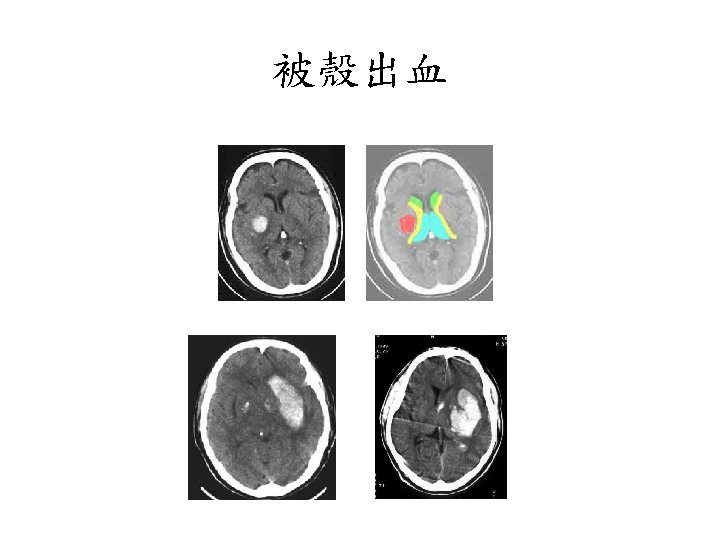

被殼出血 • • Flaccid hemiplegia Complete hemisensory deficit Homonymous hemianopsia Paralysis of conjugate gaze to the side opposite the lesion • Mild to moderate impairment of consciousness with or without headache and vomiting • Neuropsychological disorders (in some cases).